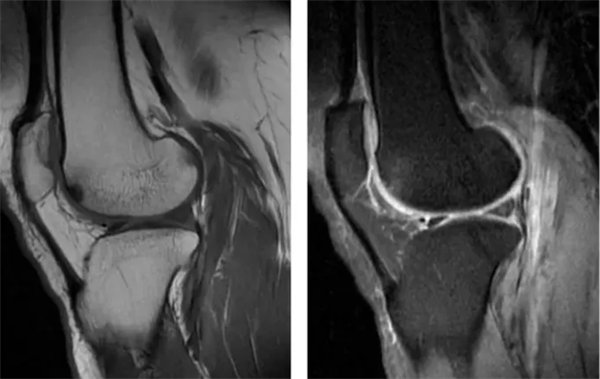

图3

原始图,正常关节软骨T2mapping成像,同一患者。

图4

定量图,正常关节软骨T2mapping成像,关节软骨T2值37~41ms,同一患者。